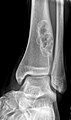

Radiology

- Sharply demarcated, lucent, loculated, meta-diaphyseal lesion.

- Surrounded by a rim of sclerotic bone.